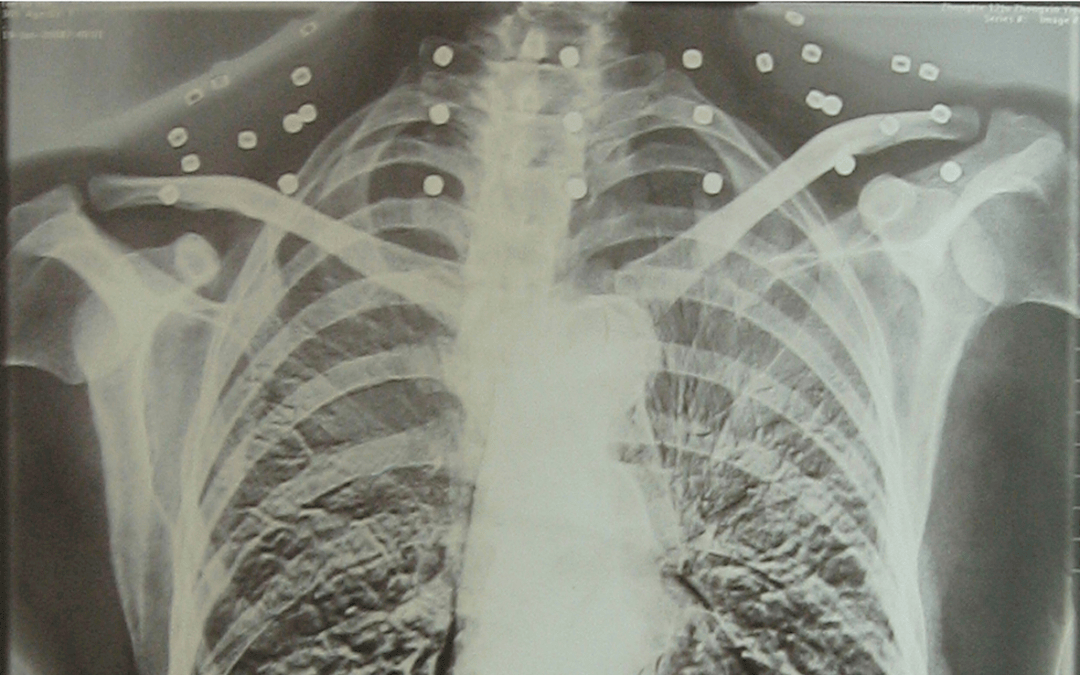

这张照片

是今年82岁的吴以先老人

拍摄的一张CT照

吴以先的颈部和腹部

共分布着33枚弹片

皇冠信用怎么弄 他体内的弹片都没有取出

身体留有弹片的位置就有痛感

但吴以先不考虑取出弹片

在皇冠信用怎么弄 他看来

这是皇冠信用怎么弄 他与战友并肩作战的见证

是皇冠信用怎么弄 他的勋章